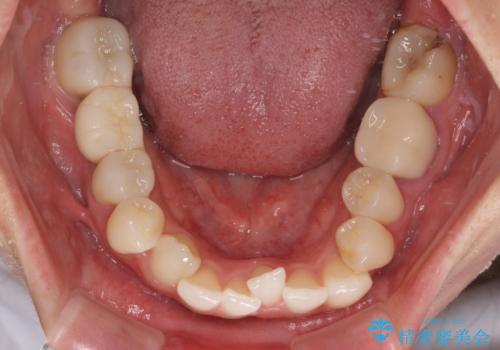

ワーキングホリデー前にきれいな歯列に

- 2、3年後にワーキングホリデーで海外に行くため、その前に歯列やむし歯をきれいにしたいとのことで来院された患者様です。

抜歯の必要な右上の奥歯は事前に抜歯をし、インビザラインにて上下歯列を整えることとしました。

矯正治療後半に奥歯の補綴治療が必要な歯にはオールセラミッククラウンを装着し、インビザラインで最終的に仕上げることとしました。